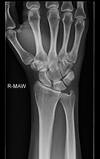

Colles’ fracture

**Colles - ‘dinner fork type deformity’** Features of the injury 1. Transverse fracture of the radius 2. 1 inch proximal to the radio-carpal joint 3. Dorsal displacement and angulation of the distal radius

Colles fracture ## Footnote Typically FOOSH forwards Extra-articular radial # with dorsal (posterior / back of hand) angulation and displacement

10